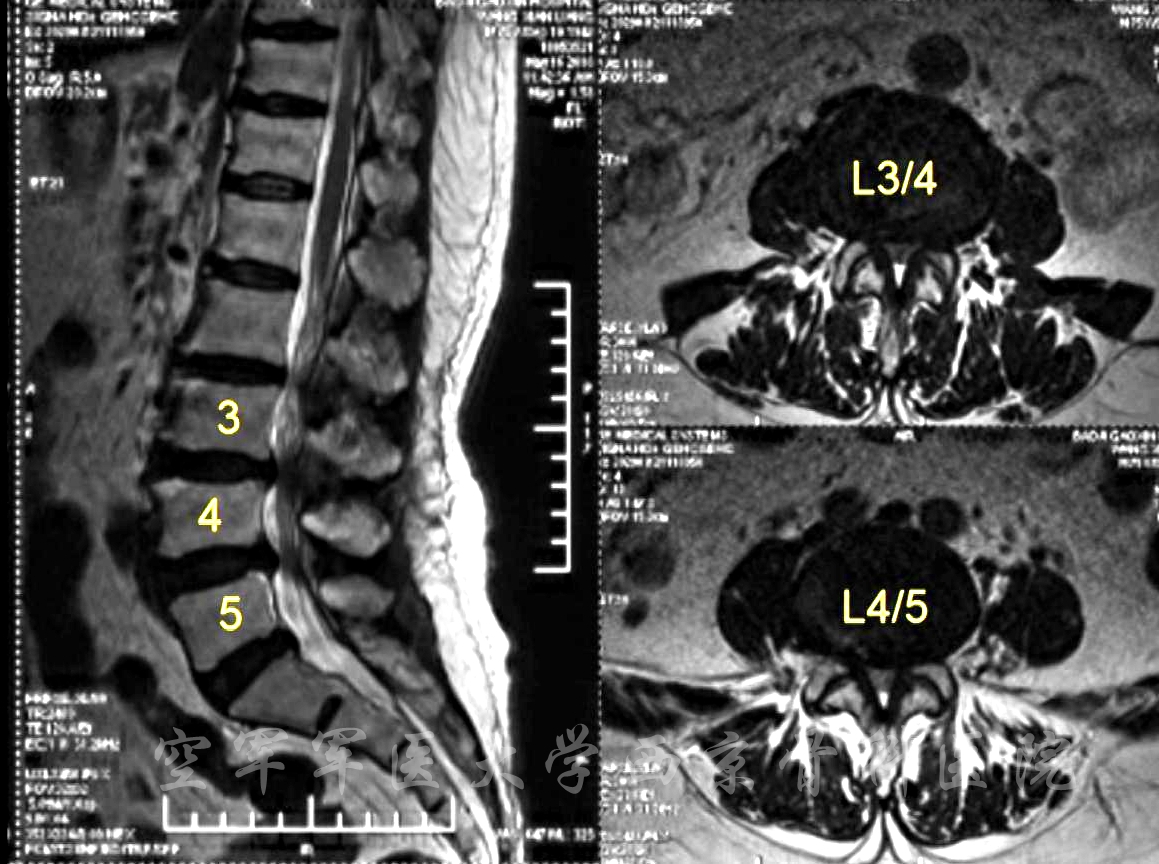

术前MRI

术前CT